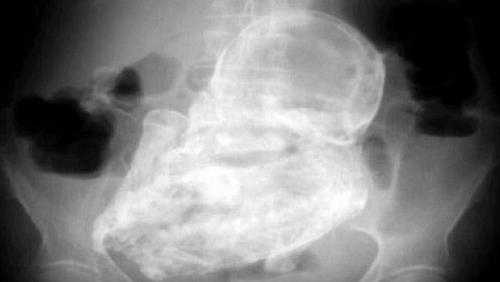

(VTC News) - Bệnh viện Đa khoa tỉnh Khánh Hòa đã phối hợp với Bệnh viện Đa khoa khu vực Cam Ranh tổ chức cuộc hội chẩn để tìm ra hướng xử lý đối với trường hợp thai đá hiếm gặp ở cụ bà 76 tuổi.

Theo đó bệnh nhân này thời gian tới sẽ được điều trị nội khoa tức là dùng thuốc để điều trị. Đây là trường hợp hiếm gặp trong y khoa và lần đầu tiên được phát hiện ở nước ta.